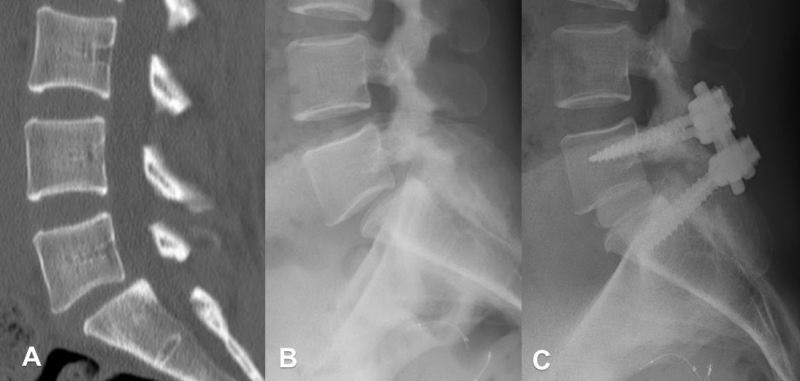

척추전방전위증의 엑스레이(x-ray) 촬영 이미지